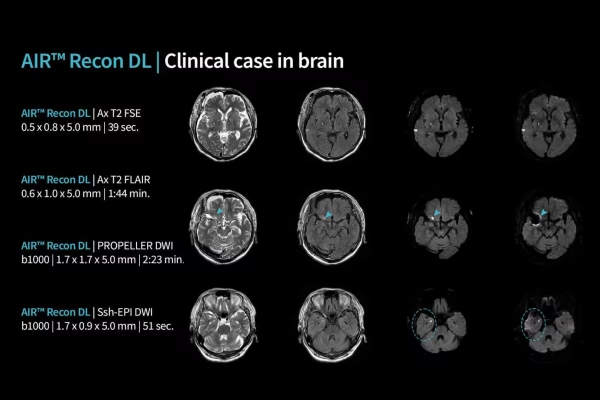

IRM GE Signa Explorer 1.5T